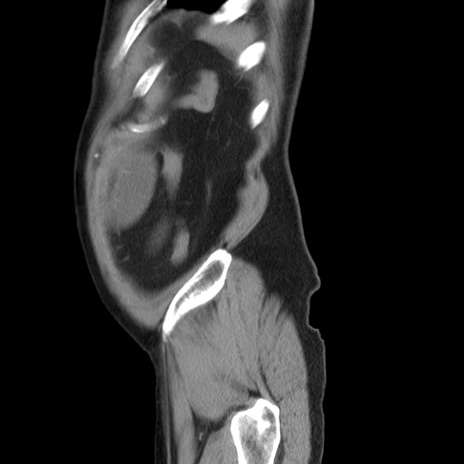

症例20(矢状断像)

【症例】 60歳代男性

【主訴】 腹部膨満、嘔吐

【現病歴】5日前頃より倦怠感を認め食事量減少し4日前の朝嘔吐、食事摂取困難となった。 3日前近医受診し点滴施行され整腸剤などを処方された。 当日他院を受診し、腹部膨満著明、炎症反応の上昇(CRP10.8、WBC11200)あり、紹介受診となる。

【身体所見】 意識JCS1 受け答えがはっきりしないBP 111/57mHg、 P 67bpm、、BT35.2°C、SpO2 97%(RA)、 腹部:膨隆、打診で鼓音あり、全体的に圧痛有り、腸蠕動音(-)、反跳痛ははっきりせず。

【データ】WBC 11400、CRP 14.20